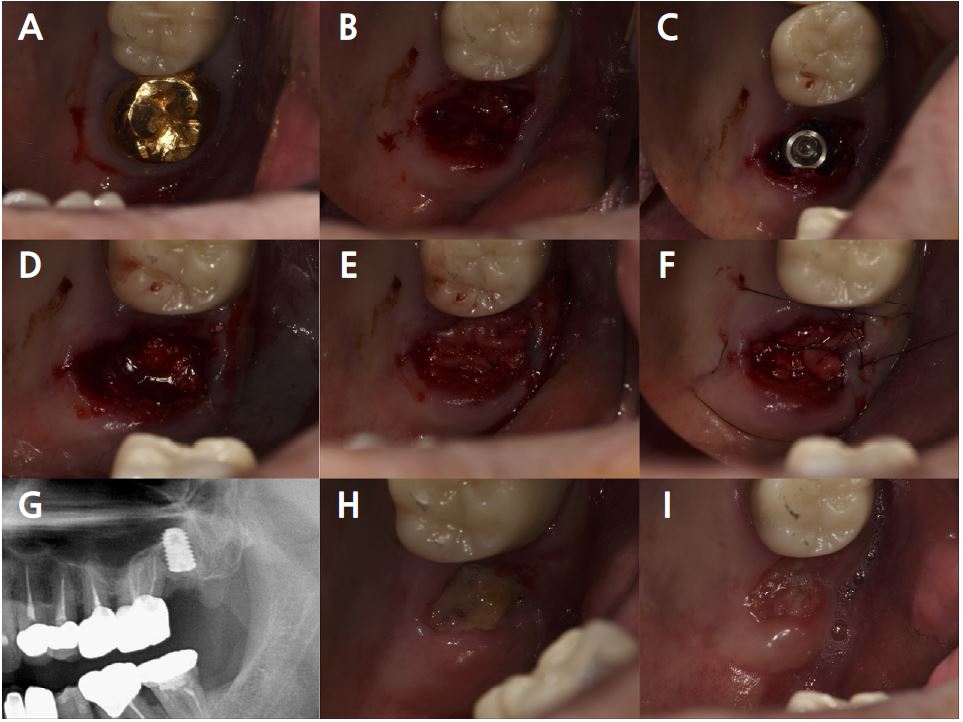

Clinical examination revealed bleeding on probing with a 7 mm PD of the buccal furcation of the maxillary right first molar (#16). Radiographic examination confirmed apically involved alveolar bone loss in the buccal roots of the mandibular first molars. (Fig. 7). It was assumed that initial stability could be achieved in the apical and septal bones, and extraction and iARP were planned. The patient was instructed to rinse with 0.12% chlorhexidine digluconate solution for 2 minutes for oral disinfection. The tooth was extracted using luxators and extraction forceps under local anesthesia with 2% lidocaine containing 1:80,000 epinephrine (Fig. 8A, 8B). After debridement of granulation tissues and irrigation with a sterile normal saline solution, immediate implant placement at the septal bone (TS III 5.0 × 8.5 mm; OSSTEM) was performed (Fig. 8C). The ISQ value at 1st surgery was 60. The gap between the implant surface and the extraction socket wall was filled with DBBM and covered with NBCM in a double-layer fashion (Fig. 8D). Thereafter, the hidden X suture and horizontal mattress suture were placed over NBCM without primary wound closure (Fig. 8E, 8F). Fourteen days after surgery, the patient returned for suture removal and postoperative examination. A delayed healing pattern with yellowish granulation tissue above the extraction socket was observed, and a depressed healing pattern of soft tissue with exposure to the cover screw was observed even after four weeks (Fig. 8G, 8H).

Fig. 8.

Case 2: Clinical photographs of the immediate implant placement with alveolar ridge preservation. (A) Initial clinical photograph of the maxillary right first molar, (B) Buccal gingival tears observed after tooth extraction, (C) Immediate implant placement in the septal bone, (D) Deproteinized bovine bone mineral was placed in the extraction socket, (E) Hidden X and horizontal mattress sutures are placed over the native bilayer collagen membrane, (F) Panoramic radiograph after implant placement, (G) Delayed gingival healing with yellowish granulation tissue observed at stitch out (2 weeks), (H) Cover screw exposure with depressed gingival healing was observed during a recall check (4 weeks).